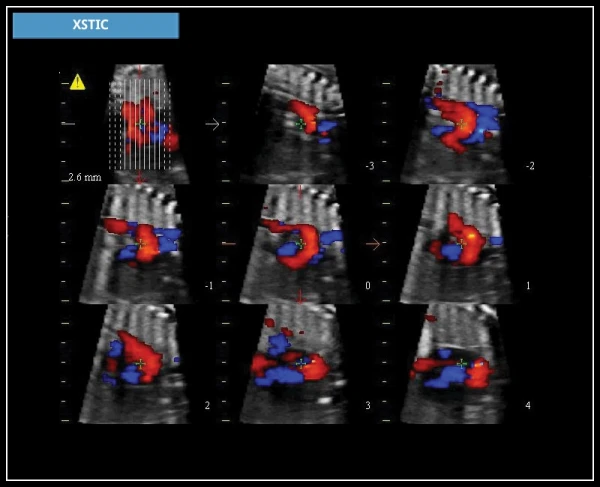

XSTIC: Программное обеспечение для реконструкции плода, предназначенное для объемной реконструкции в В-режиме и цветной/энергетической диагностики полостей сердца плода.